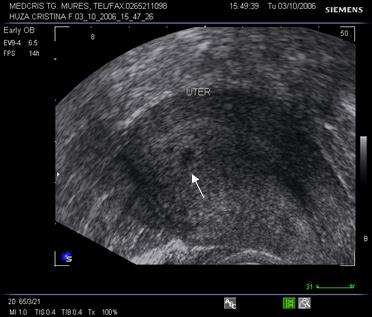

Fig. Nr.7. Sac gestational intrauterin ( cu sageata ) la ecografia transvaginala, coroana trofoblastica